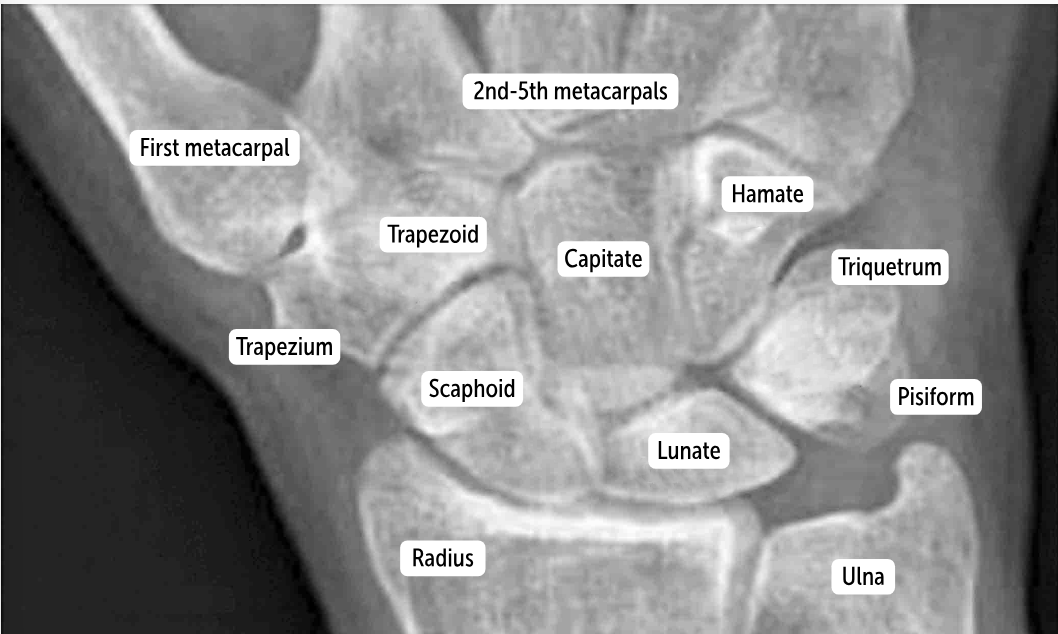

The most commonly fractured carpal bone by falling on an outstretched hand, which has a risk of avascular necrosis, is the __________.

Scaphoid bone

The most commonly dislocated bone after a fall on an outstretched hand is the ___________.

Lunate bone

Carpal bones by row:

So Long To Pinky, Here Comes The Thumb

Scaphoid, Lunate, Triquetrum, Pisiform, Hamate, Capitate, Trapezoid, Trapezium

Scaphoid

Lunate

Triquetrum

Pisiform

Hamate

Capitate

Trapezoid

Trapezium

Which carpal bones articulate with the metacarpal bones?

The bones of the distal row (hamate, capitate, trapezoid, and trapezium) articulate with the metacarpal bones.